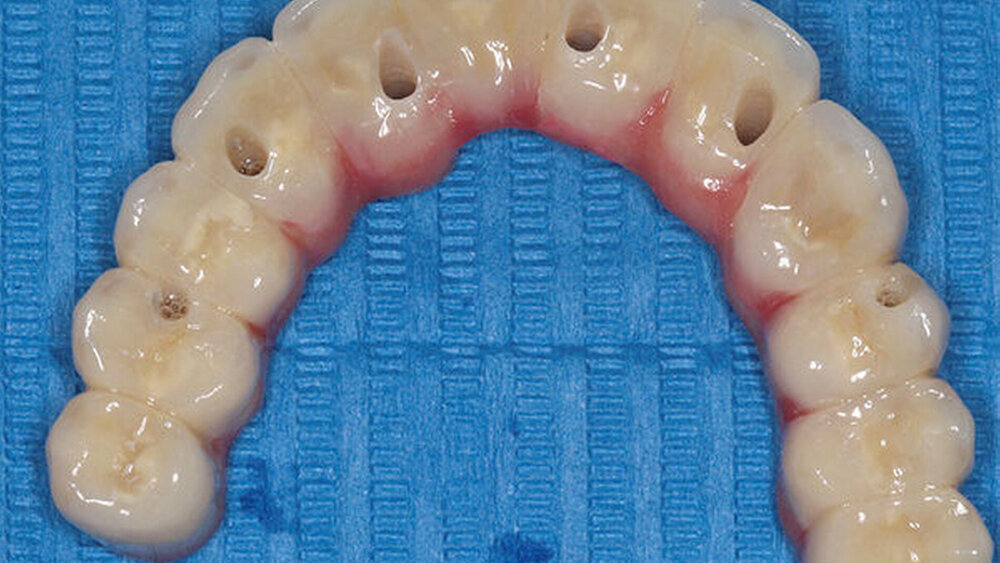

Buhtz: Korrekt, die Voraussetzung ist lediglich die Generierung von DICOM- und STL-Daten, die im Computer exakt übereinandergelegt werden können. Dann erfolgen die Behandlungsplanung wie gewohnt mit ICX-Magellan und die provisorische ‧Versorgung mit dem präfabizierten, chairside hergestellten verklebten PMMA-Provisorium (ICX-‧Smile‧bridge). Seit eineinhalb Jahren arbeiten wir zudem mit dem medentis Fräszentrum Denta5 zusammen.

Buhtz: Wir schicken die Scan-Daten, ein Wax-up und ggf. das Modell mit den Laborimplantaten an das medentis-Fräszentrum und erhalten zwei Tage später die verschraubte Unterkonstruktion. Denta 5 gibt es bereits seit einigen Jahren. Doch erst seit wir einen eigenen Modellscanner haben, stellen wir verschraubte Brücken auf diese Weise her. Jetzt habe ich eine Zahntechnikerin, die damit gut klarkommt. Full-arch-Versorgungen sind bei uns allerdings nicht das Tagesgeschäft, wir machen das vielleicht zehn- bis zwanzigmal pro Jahr. Unsere Patientenklientel ist in der Regel nicht zahnlos.

Die ideal prothetisch ausgerichtete Implantatposition ist der wohl wichtigste Erfolgsfaktor in der Implantologie. Mit ICX-Magellan lässt sich das einfach, schnell und kostengünstig realisieren.